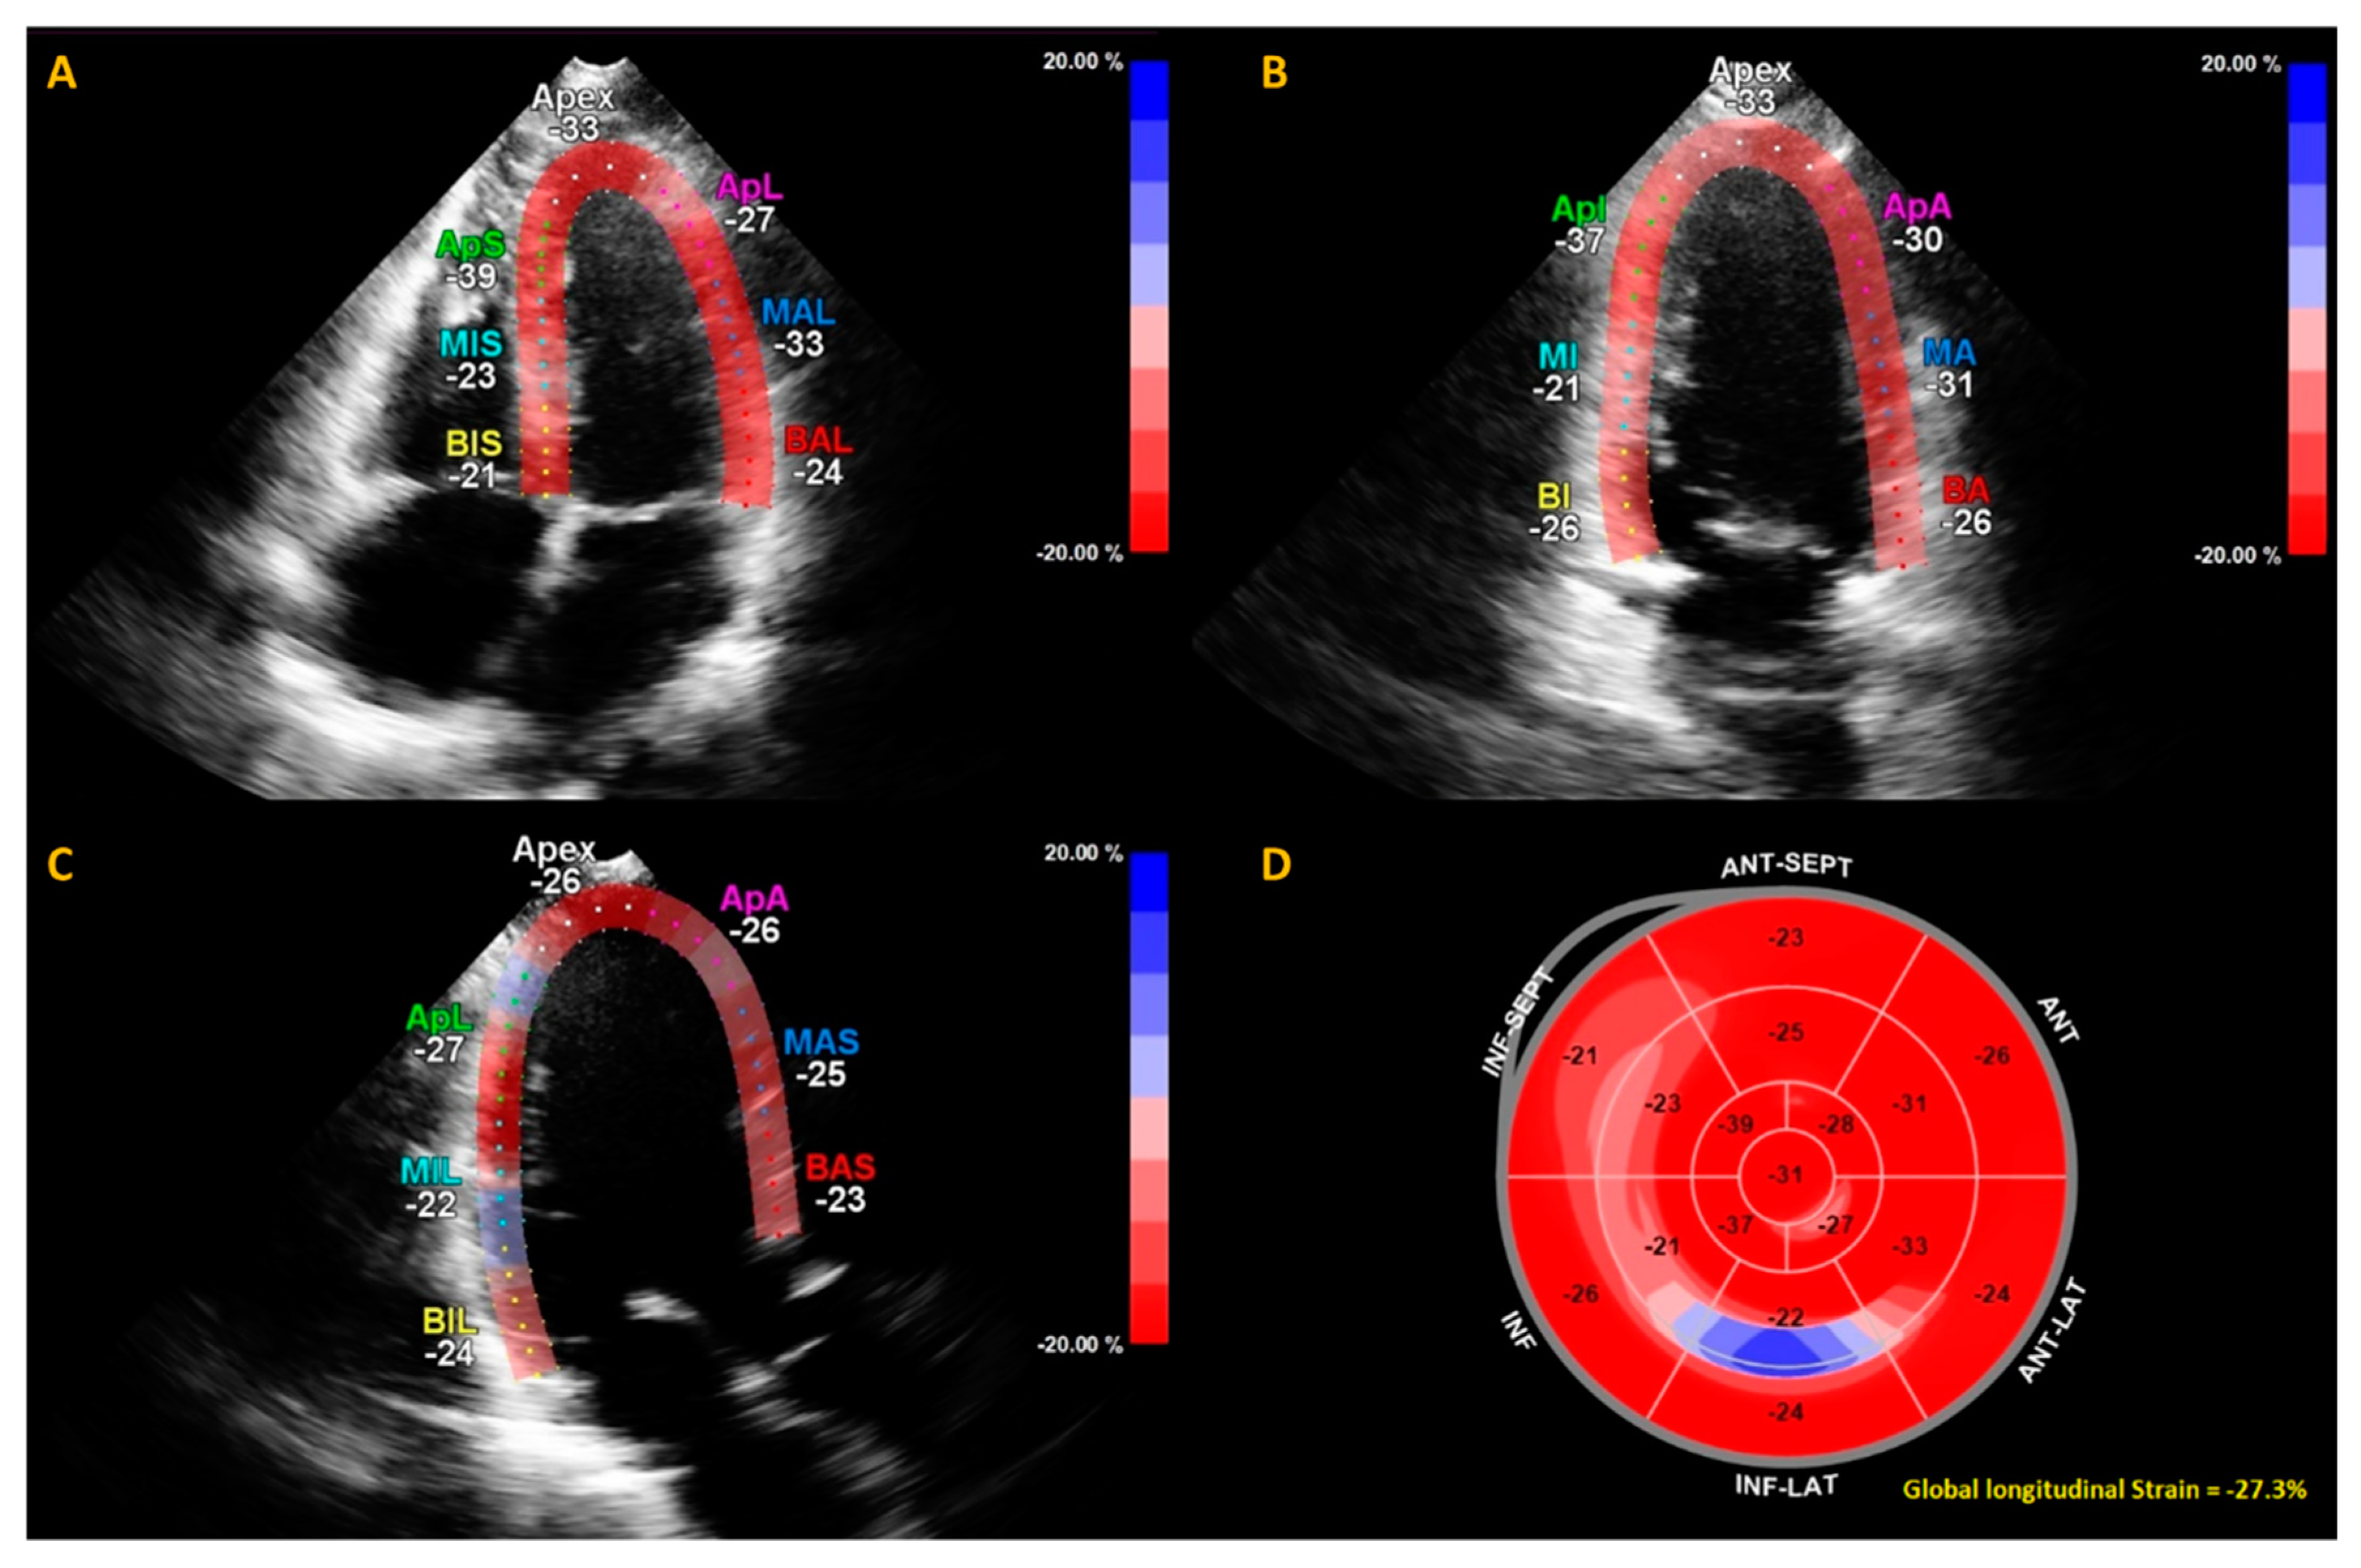

| GLS (n = 44) | −19.8 (±3.5) |

| Impaired GLS (>−17%) (n, %) (n = 44) | 6 (14%) |

| GLS | −19.8 (±3.5) | −19.9 (±2.6) | 0.79 |